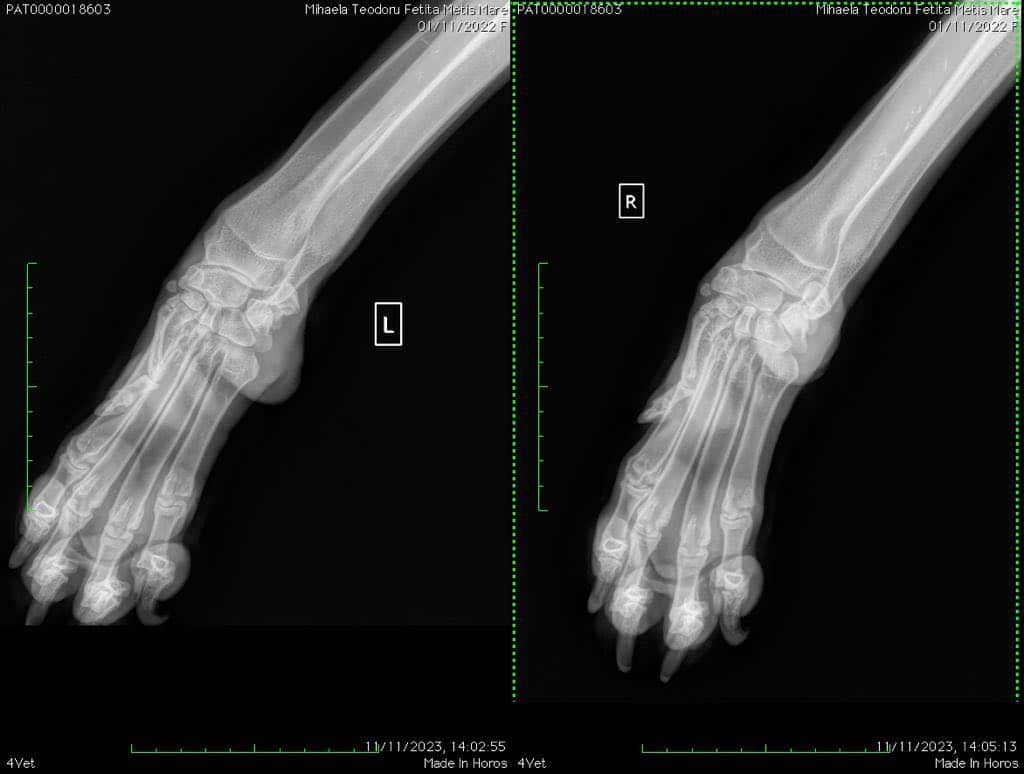

Die nette SACHI wird zur Zeit (12/2023) in einer Klinik in Bukarest behandelt. Sie hat eine extreme Hyperextension der Karpalgelenke (Durchtrittigkeit) und muss deswegen Orthesen tragen, die die Beine in der richtigen Position halten. Sie bekommt zur Zeit Kalzium und Gelenkspritzen. Die Orthesen sollte sie laut rumänischem Arzt 6 Monate lang tragen und sie wird sich dann hoffentlich ohne Operation erholen. Wenn sie die Orthesen trägt, sollte sie beaufsichtigt werden, damit sie nicht darauf herumkaut.